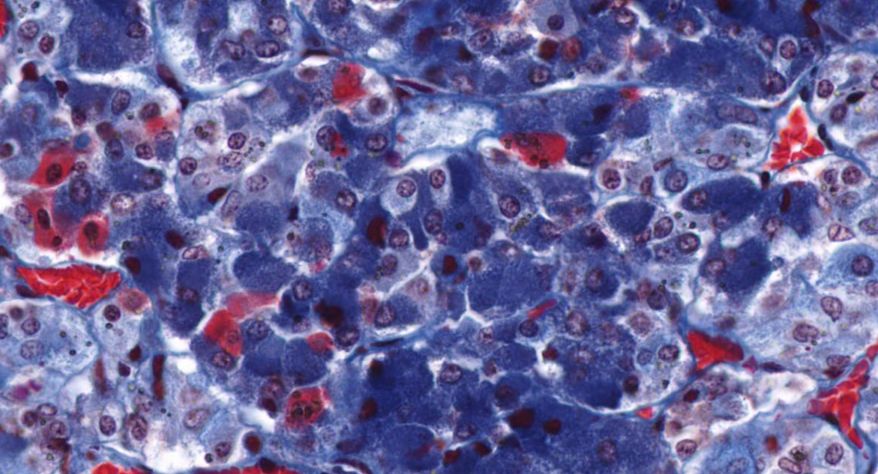

低倍镜:分出皮质及髓质。皮质由表至里分为三个带:高倍镜:(1)皮质:①球状带的细胞聚集成球状团块,细胞较小,矮柱状或多边形,核小,着色深,胞质弱嗜碱性,有少量脂滴。②束状带很厚,细胞排列成束状,在细胞之间有少量结缔组织及丰富的血窦,高倍镜观察束状带的细胞体积较大,呈多边形,核大而着色浅,胞质有许多脂滴,在制片过程中被溶解,因此胞质染色很淡。③网状带细胞排列成索,细胞索互相吻合成网,索间有丰富的血窦,胞质染色略呈嗜酸性,脂滴很少,核小着色浅。(2)髓质:髓质和皮质交界参差不齐,髓质细胞较大,呈多边形,此外还有少量交感神经节细胞,后者胞体较大,胞质着色浅,常单个或2~3个成群散布于髓质内。

1.全景图

2.被膜

3.皮质

4.球状带(10x)

5.球状带(40x)

6.束状带(10x)

7束状带(40x)

8.网状带(10x)

9.网状带(40x)

10.网状带细胞内脂褐素

11.髓质

12.嗜铬细胞

13.交感神经节细胞

14.中央静脉